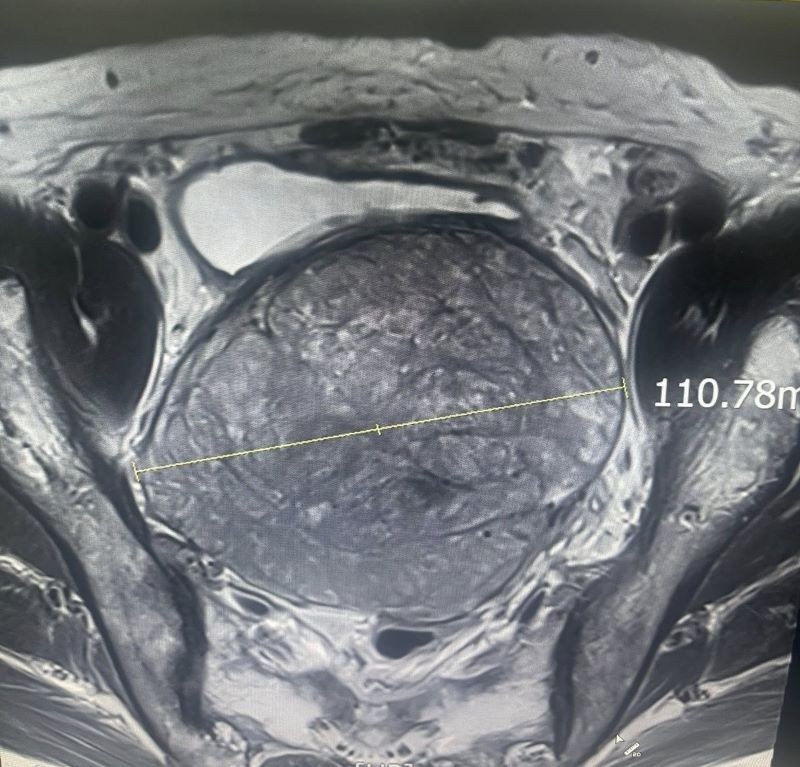

Khối u có kích thước khổng lồ trên phim chụp - Ảnh BVCC

Kích thước khối u khổng lồ trên phim chụp - Ảnh BVCC